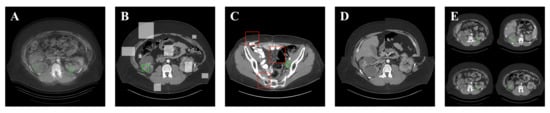

In addition to the above, we also use the Mosaic [] method. This method might employ numerous images at the same time. The most notable merit of this method is that it can embellish the discovered objects’ backgrounds. The above data augmentation methods are used to maximize the robustness and detection performance of the model. Figure 3 shows the effect of applying these methods.

Figure 3.

Illustration of different data augmentation methods. (A) series-Mixup; (B) Random-erase; (C) CutMix; (D) Mosaic; (E) source images.